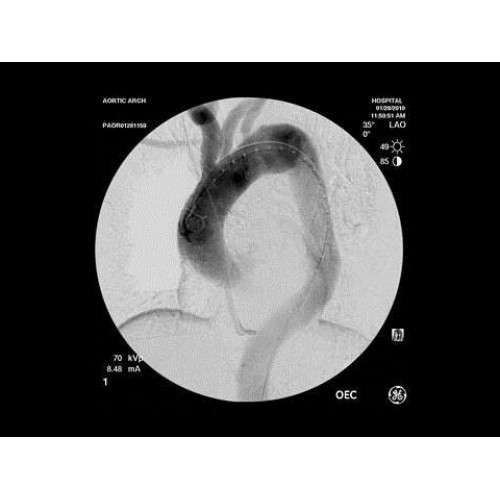

В ведущих медицинских центрах GE OEC 9900 Elite успешно применяется для проведения сложных кардиологических, нейрохирургических и ортопедических вмешательств. Система доказала свою эффективность при выполнении стентирования коронарных артерий, эмболизации сосудов головного мозга и вертебропластики. Многие учреждения отмечают повышение качества операций после внедрения этого оборудования.